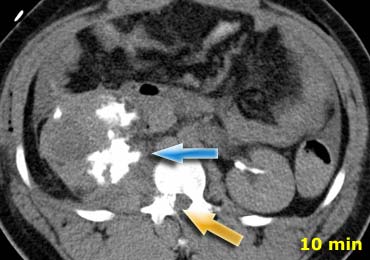

Bên trái là một bệnh nhân khác với chấn thương xuyên thấu do vết đâm dao ở hông.

CT cho thấy rõ ràng rằng tổn thương giới hạn trong khoang sau phúc mạc với khối máu tụ nhỏ quanh thận.

Không có dấu hiệu vi phạm phúc mạc và trên hình ảnh pha muộn (không hiển thị) không có hiện tượng thoát thuốc cản quang từ hệ thống thu thập nước tiểu.

Bệnh nhân này sẽ được điều trị bảo tồn không phẫu thuật